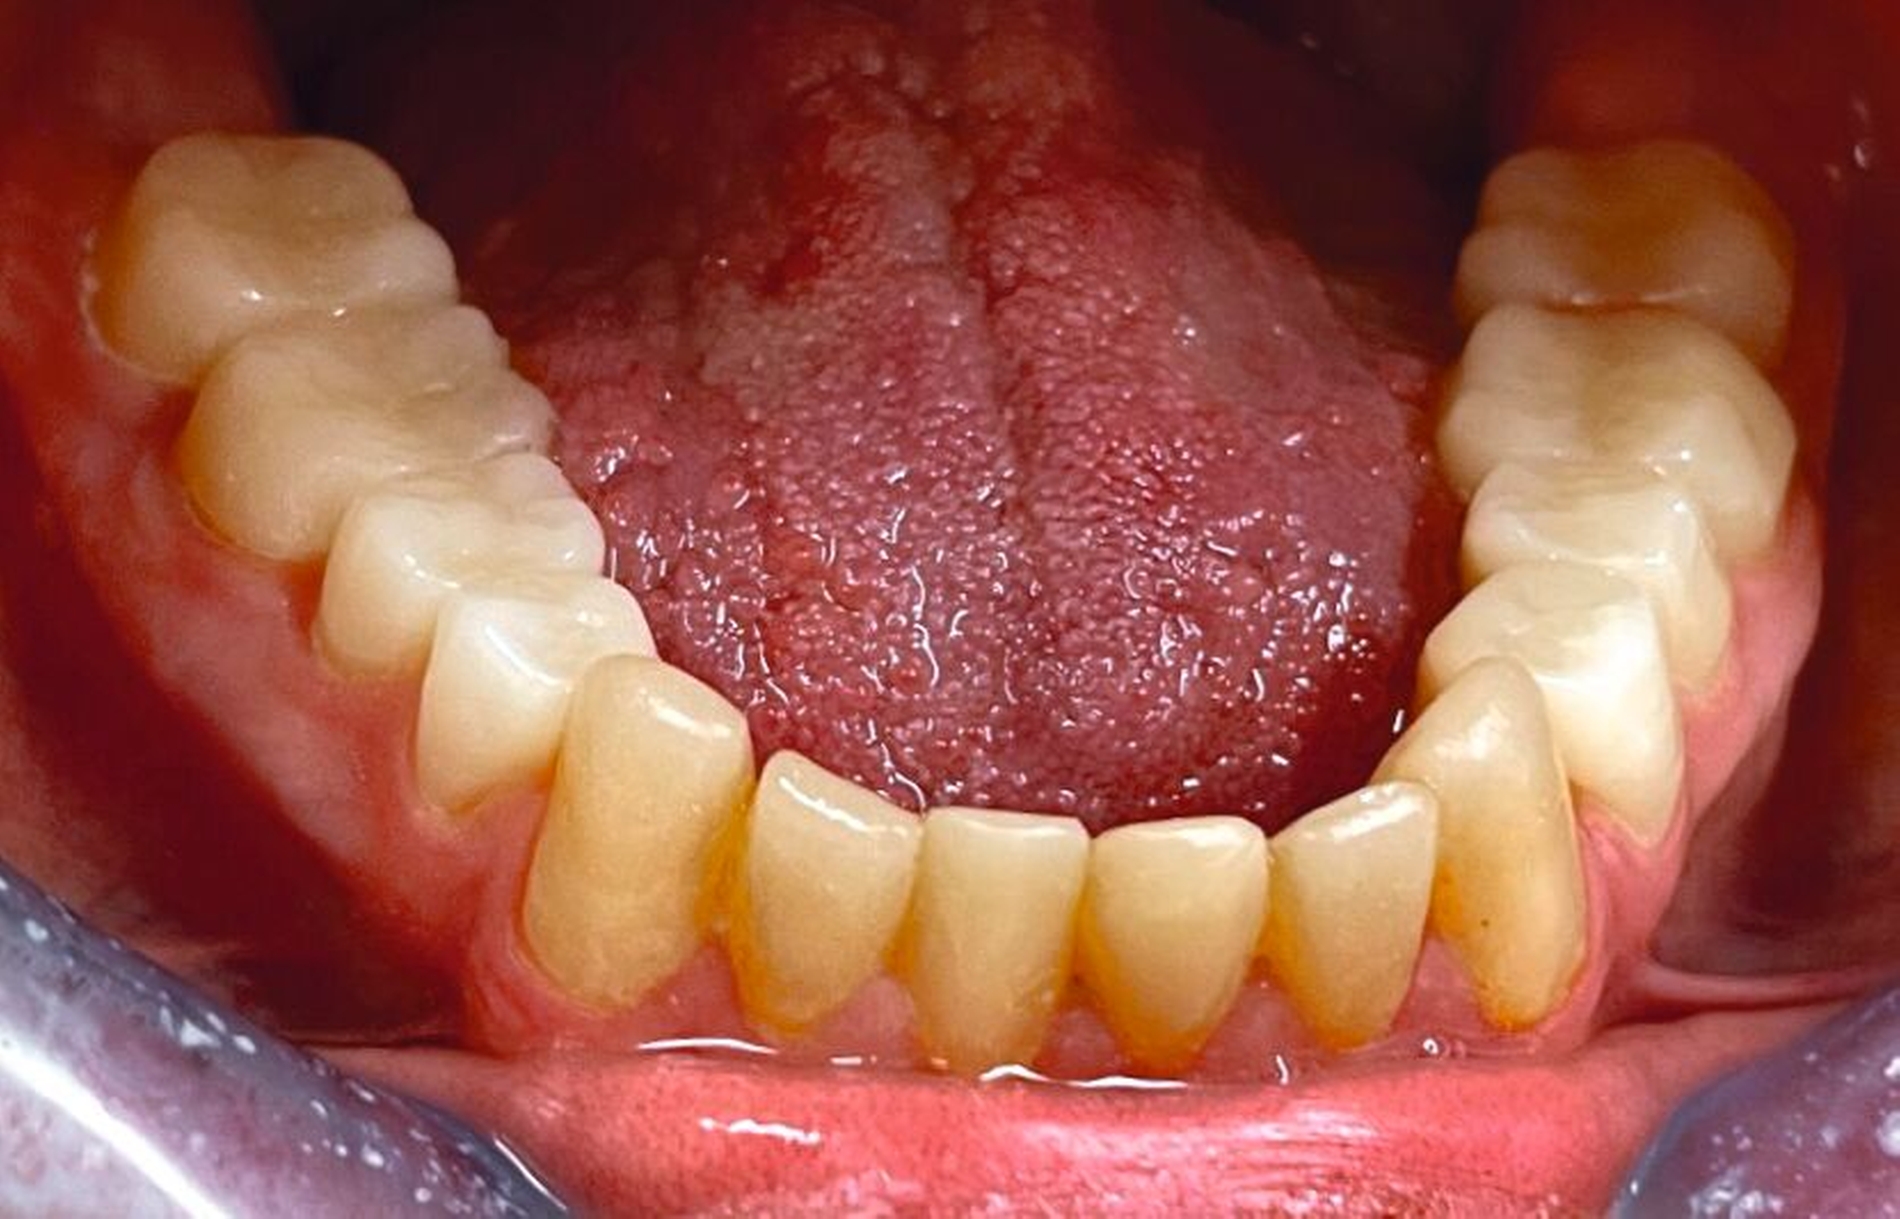

Klinisch zeigten sich ein nicht-kariöses Wechselgebiss mit generalisierter Schmelzhypoplasie an allen Zähnen sowie eine insuffiziente Mundhygiene. Zusätzlich bestanden eine fehlende Mittellinienübereinstimmung, ein Overbite von minus vier Millimetern und ein Overjet von sechs Millimetern (Abbildung 5), die sich phonetisch in einem interdentalen Sigmatismus äußerten. Röntgenologisch waren alle Zähne angelegt, jedoch war der Zahnschmelz stark reduziert oder vollständig fehlend (Abbildung 6).

Die restaurative Versorgung erfolgte in zwei Phasen: Die Frontzähne wurden im Jahr 2018 (Abbildungen 7 und 8), die Seitenzähne im Jahr 2023 behandelt (Abbildungen 9 bis 12). Im Jahr 2018 fiel die Therapieentscheidung auf indirekte Restaurationen, da eine mangelnde Adhärenz des Patienten vorlag, die sich in geringer Geduld für längere Sitzungen äußerte. Zudem war über einen längeren Zeitraum keine zuverlässige Trockenlegung möglich. Durch diese Vorgehensweise konnten die Anzahl und die Dauer der Behandlungstermine reduziert werden.